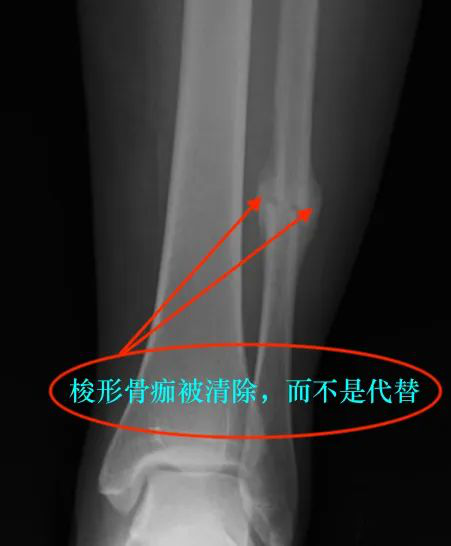

但需要注意一点,当骨折对位好后,梭形骨痂被清除,而不是代替。

如果骨折被骨皮质嵌入形成愈合,部分梭形骨痂变为骨密质,形成新的骨皮质,而剩余部分被吸收,在新生成骨皮质深面的大量老骨皮质也被吸收,转变为新的骨小梁结构。